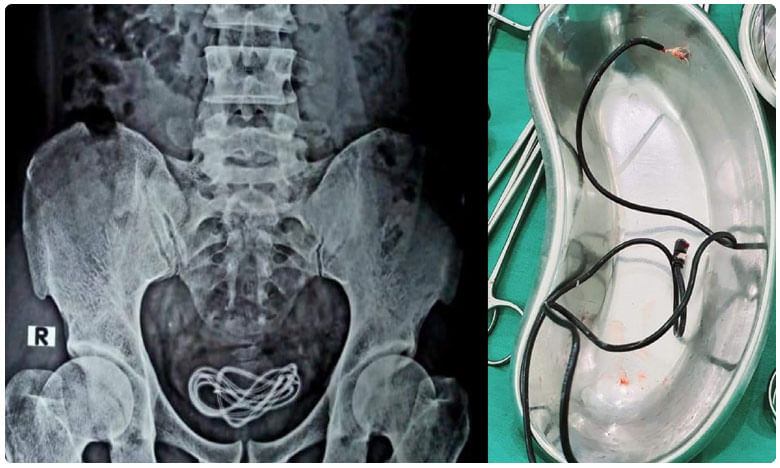

ఓ వ్యక్తి మూత్రాశయం నుంచి మొబైల్ ఛార్జర్ కేబుల్ని బయటకు తీశారు వైద్యులు. ఈ ఘటన అసోంలో చోటుచేసుకుంది. ఇస్లాం అనే వైద్యుడు ఈ విషయాన్ని తన ఫేస్బుక్ ద్వారా పోస్ట్ చేయడంతో ఈ ఘటన వెలుగులోకి వచ్చింది. గువాహటికి చెందిన 30 ఏళ్ల వ్యక్తి కొద్దిరోజులుగా కడుపునొప్పితో బాధపడుతూ స్థానిక ఆస్పత్రికి వెళ్లాడు. తాను పొరపాటున మొబైల్ ఛార్జర్ కేబుల్ను తిన్నట్లు వైద్యుడికి వివరించాడు. దీంతో మొదట అతనికి ఎండోస్కోపీ చేయగా.. అతని కడుపులో కేబుల్ కనిపించలేదని దాంతో స్వయంగా తానే రంగంలోకి దిగానన్నారు. ముందు ఎక్స్రే తీయగా.. అతని మూత్రాశయంలో ఛార్జర్ వైర్ చూసి షాక్ అయినట్లు పేర్కొన్నారు. వైద్యులను తప్పుదారి పట్టించేందుకు ఆ వ్యక్తి అబద్ధం చెప్పినట్లు వైద్యుడు తెలిపారు. తన పురుషాంగం ద్వారా కేబుల్ వైరస్ను చొప్పించుకున్నాడని పేర్కొన్నారు. అలాగే అతని మానసిక పరిస్థితిపై కూడా అనుమానాలున్నాయన్నారు. కాగా మొత్తానికి శస్త్ర చికిత్స చేసి కేబుల్ను బయటకు తీశామని ప్రస్తుతం అతని ఆరోగ్య పరిస్థతి నిలకడగా ఉందని డాక్టర్ ఇస్లాం వెల్లడించారు.